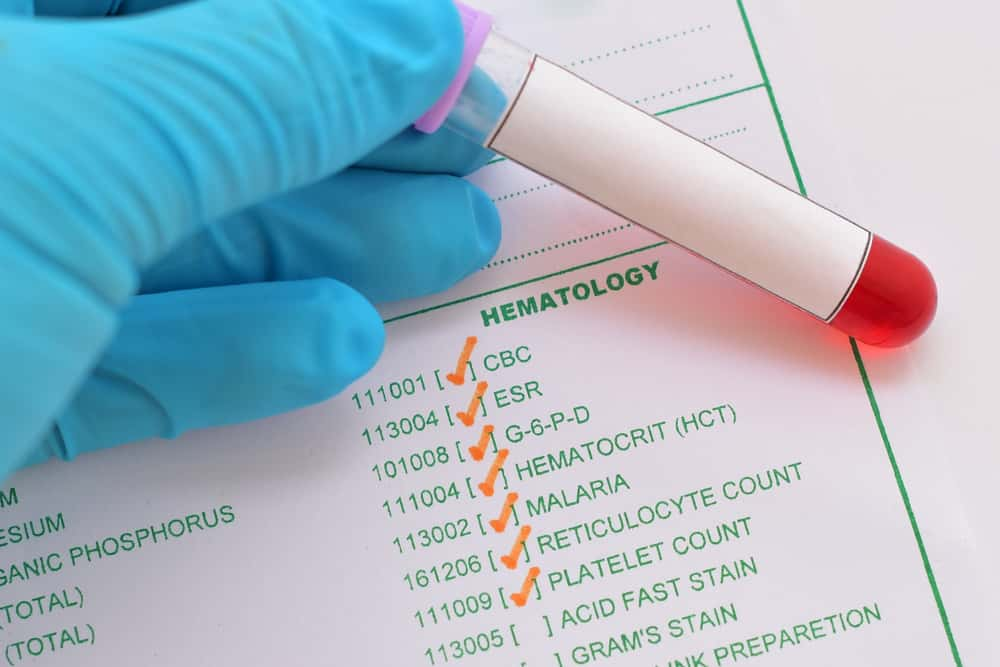

I originally went to the doctor’s because I was really tired. The doctor waved it off, but my mom insisted I should get a CBC (complete blood count). They found that my platelets were extremely low, which resulted in them running additional tests to find that I actually had acute lymphoblastic leukemia. To this day, I have no idea why my mom made me go back to get a CBC, but I’m grateful she did.